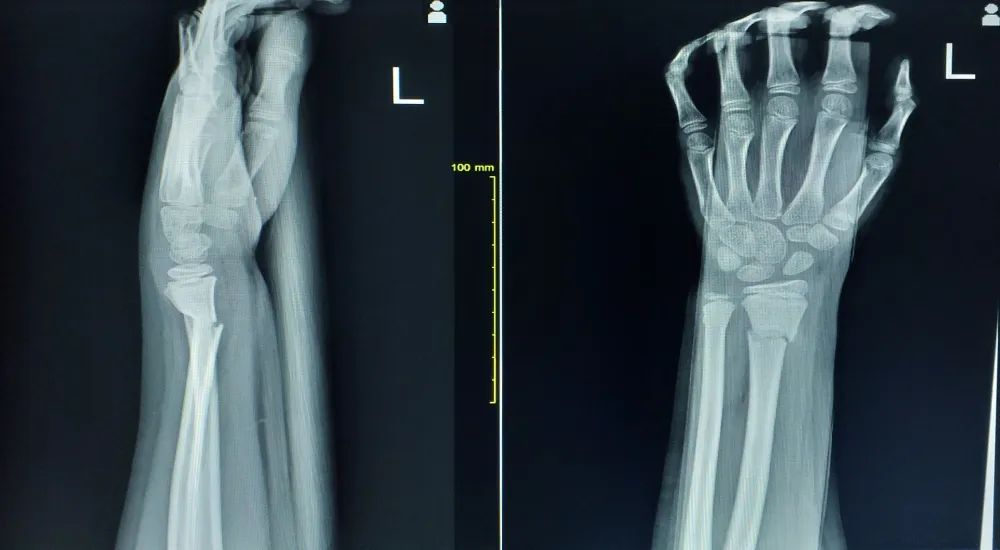

桡骨远端关节面呈由背侧向掌侧、由桡侧向尺侧的凹面, 分别形成掌倾角 (10°~15°) 和尺倾角 (20°~25°)。

图源:第八版外科书

桡骨茎突尺侧与尺骨小头桡侧构成尺桡下关节, 与尺桡上关节一起,构成前臂旋转活动的解剖学基础。

1、伸直型骨折(Colles 骨折)

Colles 骨折多为腕关节处于背伸位、手掌着地、前臂旋前时受伤。

典型畸形姿态即侧面看呈「银叉」畸形,正面看呈「枪刺样」畸形。X 线可见骨折远端向桡、背侧移位,近端向掌侧移位。

2、屈曲型骨折(Smith 骨折)

受伤时腕关节屈曲、手背着地引起,也可由于腕背部受到直接暴力打击发生。

受伤后腕部下垂,局部肿胀,腕背侧皮下瘀斑。X 线可见典型移位,近折端向背侧移位,远折端向掌侧、桡侧移位。可合并下尺桡关节损伤、尺骨茎突骨折和三角纤维软骨损伤。

3、桡骨远端关节面骨折伴腕关节脱位

桡骨远端关节面骨折伴腕关节脱位 (Barton 骨折) 是桡骨远端骨折的一种特殊类型。

在腕背伸、前臂旋前位跌倒, 手掌着地, 暴力通过腕骨传导, 撞击桡骨关节背侧发生骨折, 腕关节也随之而向背侧移位。

其发生率占全身骨折的 0.1%。临床上表现为与 Colles 折相似的「银叉畸形」及相应的体征。

X 线拍片可发现典型的移位。当跌倒时, 腕关节屈曲、手背着地受伤, 可发生与上述相反的桡骨远端掌侧关节面骨折及腕骨向掌侧移位。

这类骨折较少见, 临床上常漏诊或错误诊断为腕关节脱位。只要仔细阅读 X 线片, 诊断并不困难。